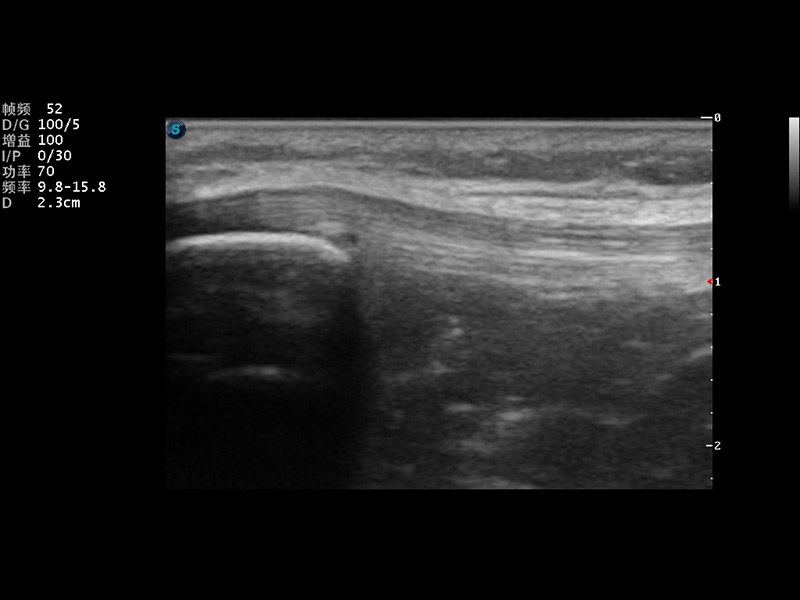

S9便携式彩色多普勒超声诊断仪是球速体育入口研发的高端便携彩超设备,外观设计新颖、产品性能卓越。S9在便携超声领域采用了突破传统的触摸屏交互设计,并以先进的软件硬件技术和设计理念,为您带来清晰的图像质量、稳定的工作性能和便捷的操作体验。